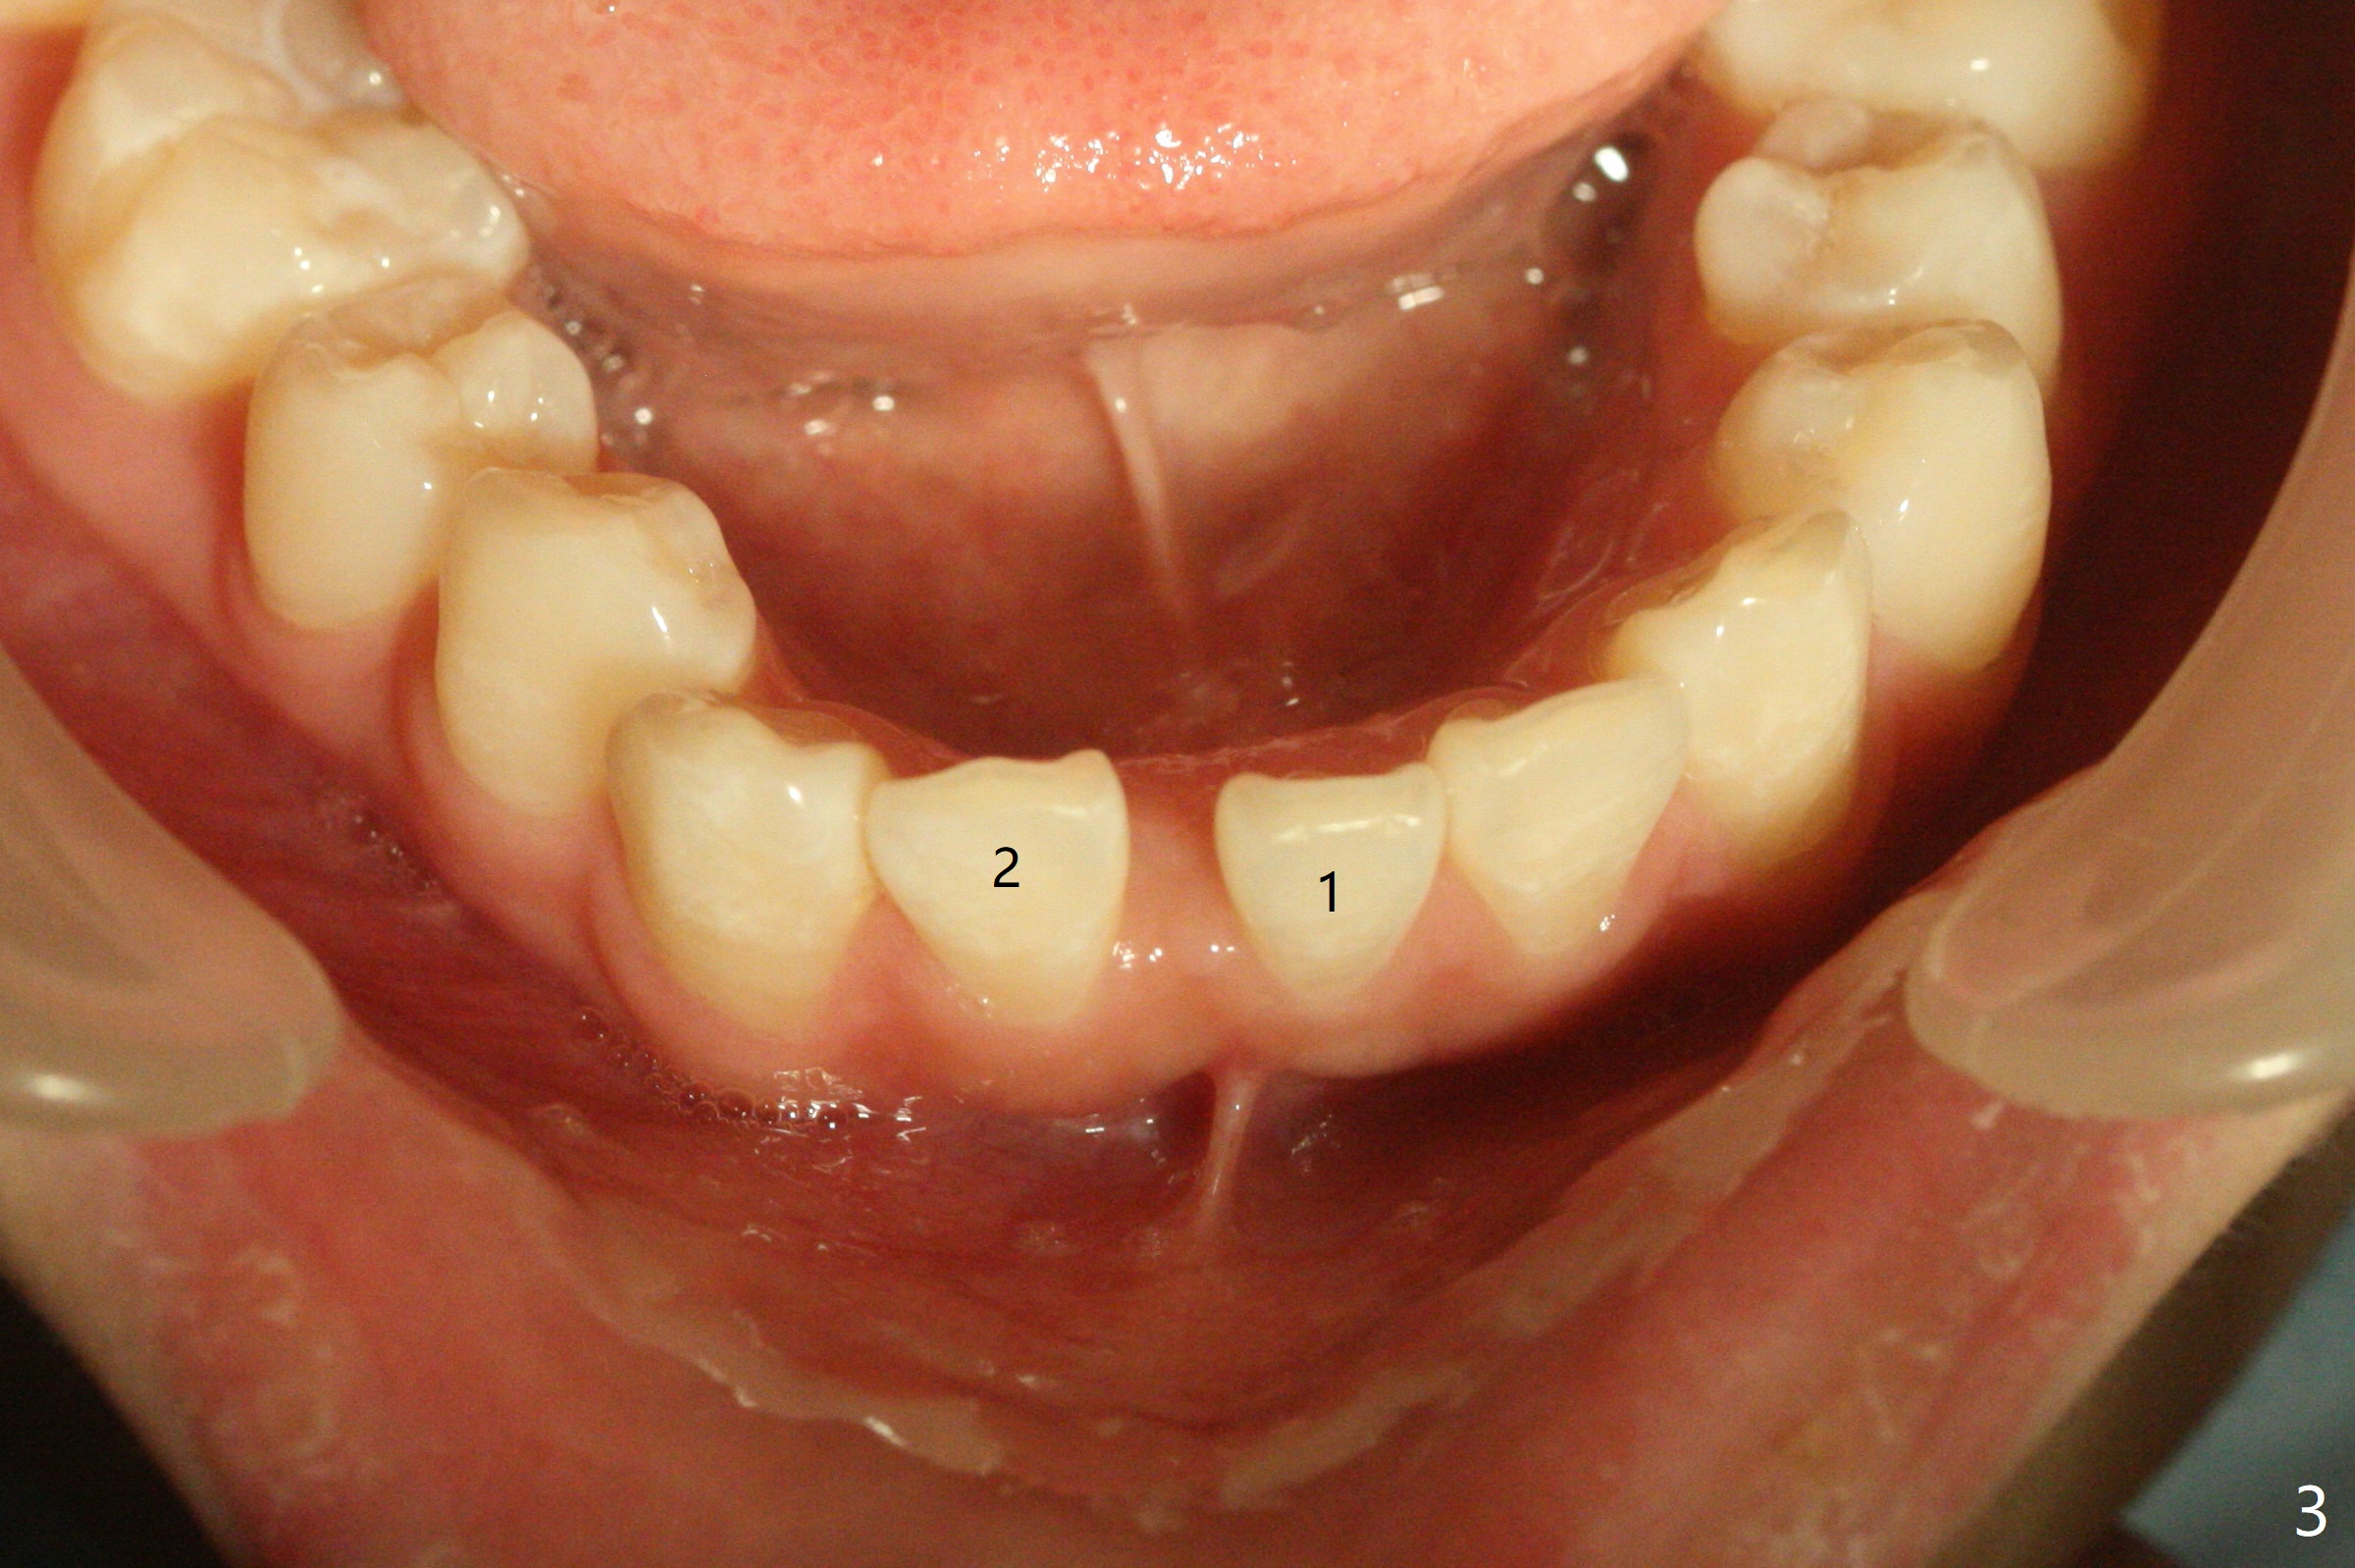

13岁女孩面型正常,先天性缺失右下1(图一,四,七),前牙深覆盖(图二),邻牙扭转(图三),治疗计划使用隐形矫正器,上牙片切,内收,关闭下切牙间隙(图八)。片切前发现上切牙邻面龋(图五,六),最大一个已经修补(右上2),不知其余小的龋坏能否片切,涂氟保守处理?不过她有龋坏易感性,以前乳牙龋坏。邻面片切后,上,下颌分别用无色和蓝色树脂做attachments(图九)。不明白的是Reciprocating saw远不如wheel利索。